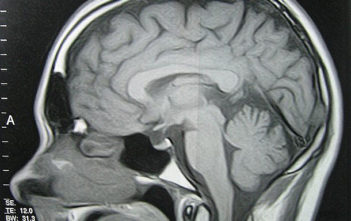

The discovery of the brains’ ‘internal GPS system” has earned three scientists the Nobel Prize of physiology or medicine.